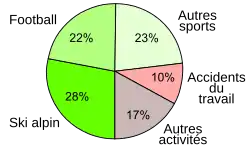

La statistique suisse des accidents (UVG), qui se fonde sur environ la moitié de tous les citoyens suisses, donne 6 350 blessures au LCA par an (1997-2001). Ceci constitue pour l'ensemble de la Suisse de 10 000 à 12 000 cas. Parmi les 6 350 blessures répertoriées, 73 % sont causées par « sports et jeux », 10 % sont des accidents du travail, les 17 % sont répartis entre diverses activités, comme les accidents de la route, accidents domestiques ou autres activités de temps libre[16].

La fraction en fréquence des divers sports sur les ruptures de LC dépend très fort des préférences locales pour chaque sport. Aux États-Unis par exemple, les proportions les plus élevées de rupture de LC sont chez les joueurs de basket 20 %, football 17 %, football américain 14 %, tandis qu'en Norvège la séquence est football 42 %, handball 26 %, ski alpin 10 %[36],[37]. En Allemagne, le trio de tête est le même qu'en Norvège[36] ; puis suivent les accidents de la route, et les accidents du travail[38]. Plus de 70 % des ruptures du LCA arrivent sans influence externe, par réception après un saut, par freinage ou changement de direction soudains[39],[40].